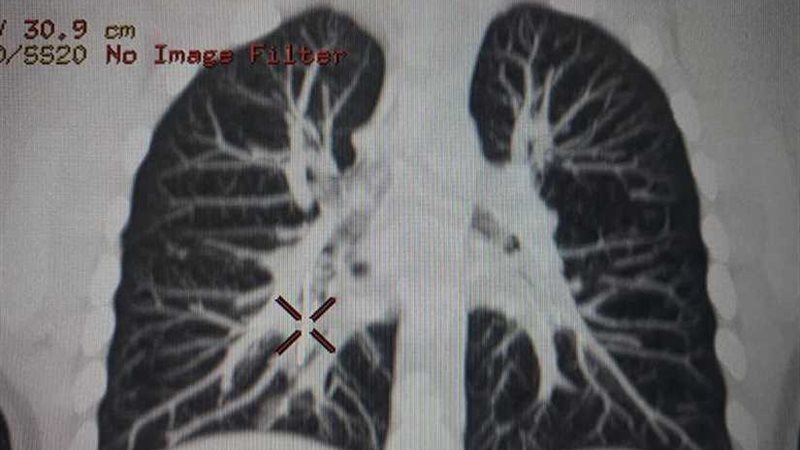

وتم عمل أشعة مقطعية على الصدر تمت مناظرتها بواسطة الدكتور أشرف عبدالرحمن، استشاري ورئيس قسم الأشعة بمستشفى الأطفال، أظهرت وجود الدبوس مدفونا في جدار القصبة الهوائية اليمنى، واقترابه الشديد من أحد الأوردة الرئوية، ما يشكل خطورة بالغة ويستوجب تدخلا سريعا.